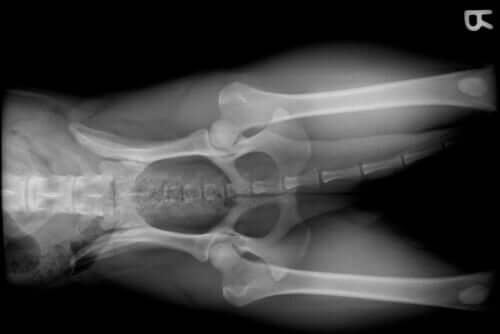

Os problemas mais comuns nas articulações dos cães

Uma das tantas razões pelas quais um cachorro visita o veterinário é o surgimento de patologias articulares. O dono costuma perceber esse problema quando o seu cão começa a mancar ou, em certas ocasiões, quando manifesta uma dor aguda.

Os problemas articulares podem aparecer por várias razões. Alguns exemplos:

- Raça. Certas raças de cães, como o pastor alemão, costumam desenvolver displasia de quadril. Por sua vez, raças como golden retriever, rottweiler ou doberman, devido ao seu grande tamanho e rápido crescimento, tendem a sofrer displasia de ombro ou cotovelo.

- Idade avançada. Do mesmo modo que ocorre com outros mamíferos, incluindo o ser humano, quando os cães chegam à velhice, surgem patologias ligadas a essa etapa da vida. Referimo-nos à doença articular degenerativa canina (DAD).

- Problemas de crescimento. O período de crescimento de um cão é um momento delicado, assim como em outras espécies. Deficiências alimentares, problemas hormonais ou a raça podem provocar danos nas articulações.

- Fraturas que envolvam uma articulação.

- Ruptura de ligamento cruzado anterior. Por sobre-esforço, excesso de exercício ou mesmo por pertencer a uma raça pequena, o ligamento cruzado anterior pode se romper. Isso acarreta sérios problemas nas articulações.

- Obesidade. Além de diminuir, e muito, a qualidade de vida do animal de estimação, a obesidade provoca, entre outras coisas, sobrecarga das articulações. Isso pode ocasionar graves problemas.

- Artrose.

- Artrite.